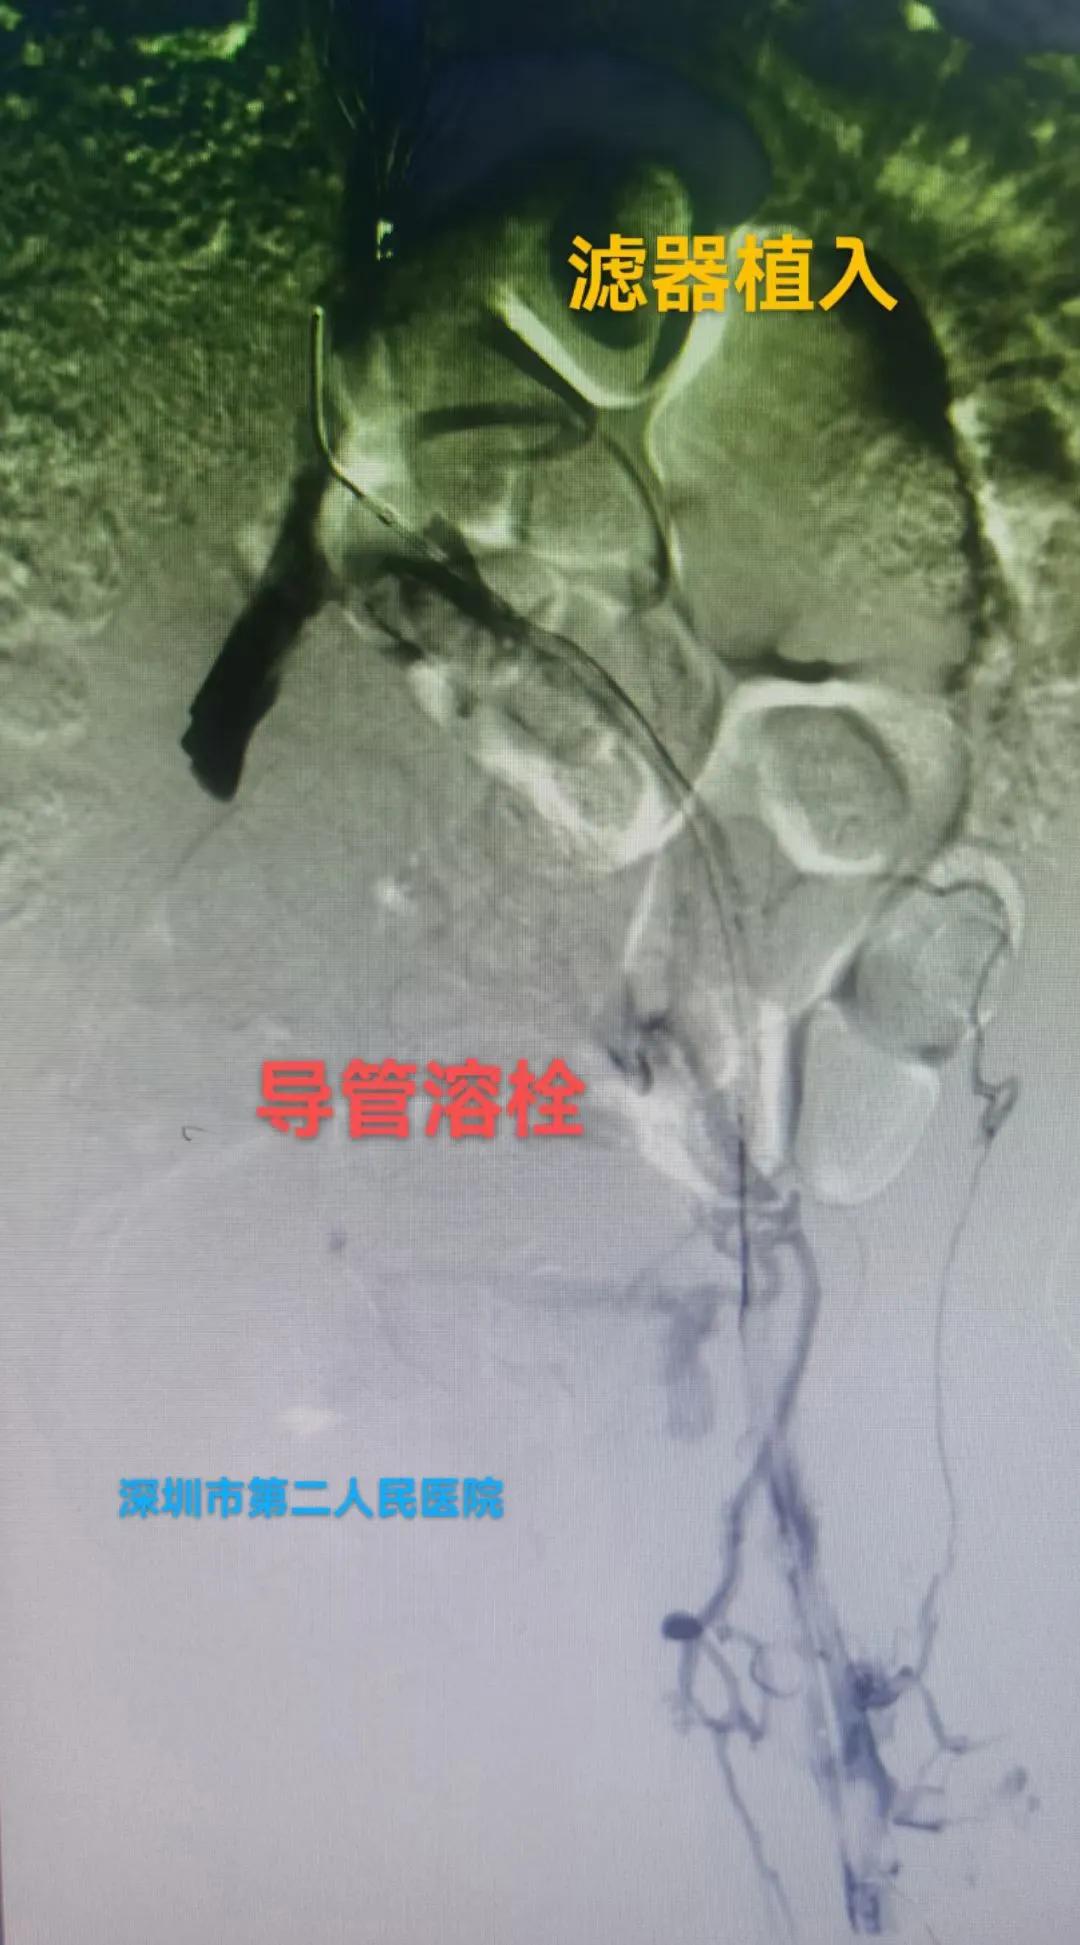

答:这个就需要根据患者自身情况制定个性化治疗策略,主要策略为:①保守抗凝治疗:②系统溶栓治疗;③导管接触性溶栓治疗;④机械性血栓清楚治疗;⑤必要时球囊扩张和支架植入治疗;⑥急危重症病人需切开取栓治疗等。

下腔静脉滤器网住血栓